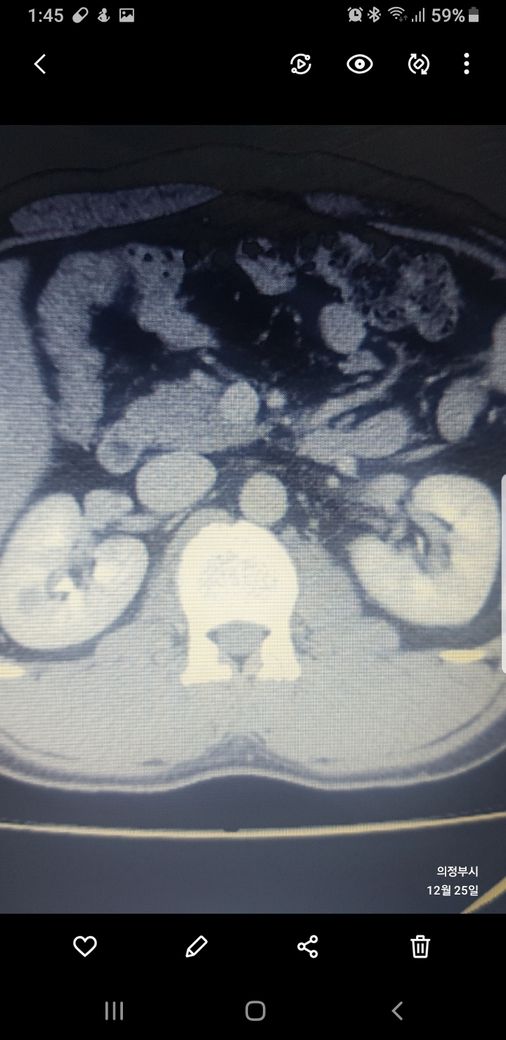

복부ct 작년 11월 , 올해 12월 촬영분입니다.

우측신장에 작년에는 1.7cm 물혹이 올해는 같은곳에 1.2cm 출혈성낭종이라는데

같은부위에 뭐가 다른건지 문제가없는건지 봐주세요.

둘다 같은 병변이고 비조영증강에서 약간의 고음영 소견이 있어 출혈성 낭종이 의심됩니다.

신장의 낭성병변의 분류에서 1, 2, 2F, 3, 4이렇게 나뉘는데, 2에 해당되는 소견입니다.

크게 걱정하실 필요는 없습니다.